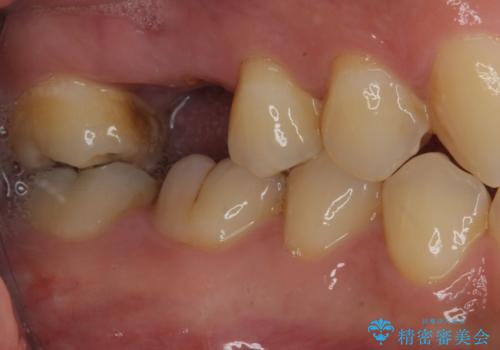

反対側の歯は、歯根だけが歯肉に埋もれて残っている状態のため、抜歯が必要な状態でした。

歯根だけとなっている歯はインプラントに、神経組織の失活している歯は根管治療を行い、いずれもオールセラミッククラウンにて補綴治療を行うこととしました。